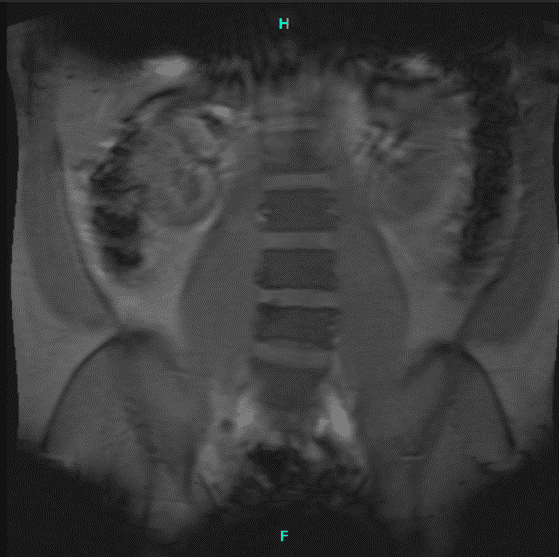

El paciente acudió con un resultado de resonancia magnética que mostró en L3-4, había protrusión discal y hernia foraminal izquierda. Hay un pinzamiento foraminal bilateral más prominente en la izquierda que en la derecha.

En L4-5, hay una protrusión discal con pinzamiento foraminal bilateral. En L5-S1, hay una hernia central de base ancha con un desgarro anular que colinda directamente con las raíces nerviosas bilaterales S1.

Resonancia magnética de columna lumbar sin contraste